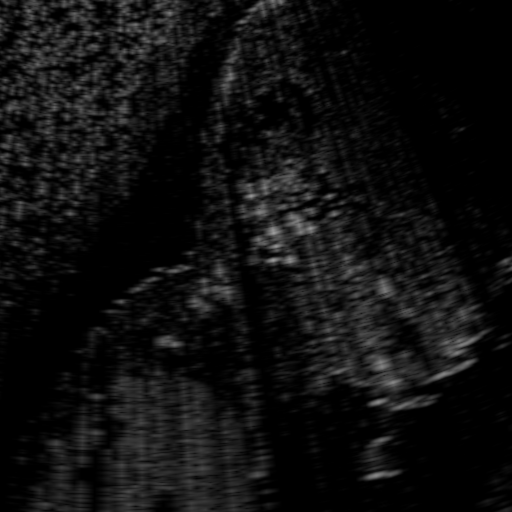

Above image translation has been demonstrated on patches. For the entire field-of-view (FoV) US images, patch fusion from image translation of non-overlapping patches would cause artifacts at image seams. Averaging overlapping patches, on the other hand, would blur the essential US texture. Although seamless tiling of US images is possible using graphical models [3], this requires prohibitively long computation time. Herein, we instead directly apply our trained generator on full FoV low-quality images, since the generator is fully convolutional and thus can operate on images of arbitrary size. Fig. 4 shows two examples of translated images by L2HMS and L2HMSA, demonstrating direct inference on full FoV images. While anatomical structures are well preserved and the effect of attenuation integral map is apparent, speckle texture appearance is seen to degrade slightly especially in the top image regions, where the ultrasound texture looking particularly different due to focusing difference and near-field effects.